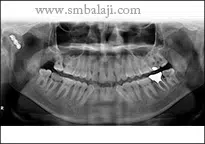

Post-surgery, the patient’s condition steadily improved. The wound healed satisfactorily, and an X-ray confirmed successful bone healing. The patient’s pain during jaw movements subsided, and his mouth opening range increased significantly. These positive outcomes were a testament to Dr. Balaji’s expertise and the patient’s commitment to recovery.